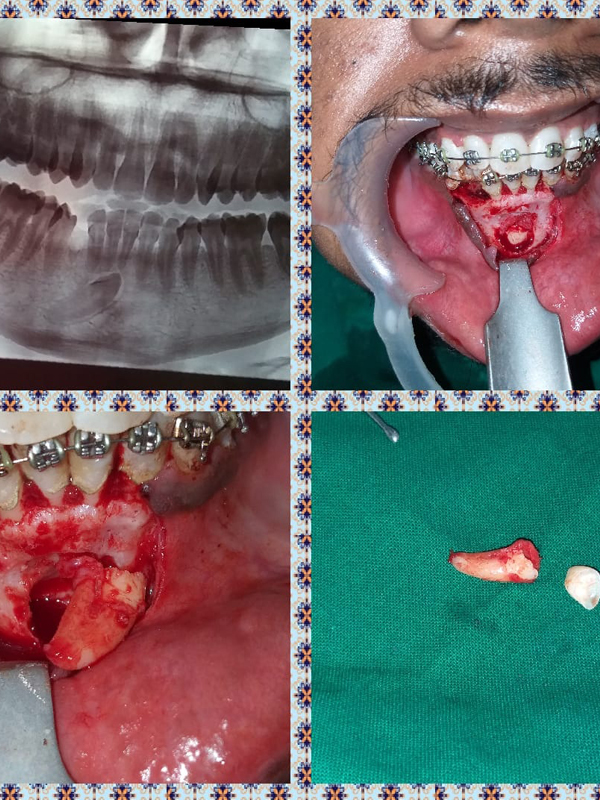

Home / Treatment Photos